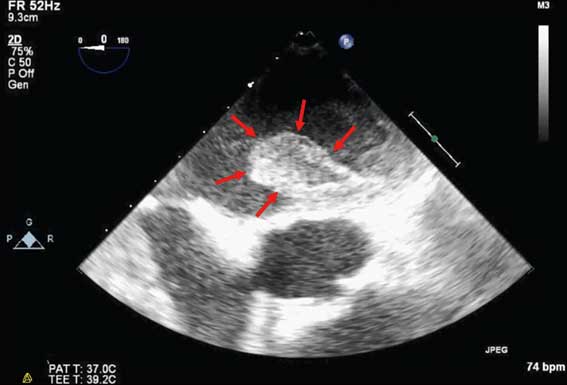

心臓の超音波画像

心房細動の左心房内血栓(赤矢印)。約3cmの大きさがある